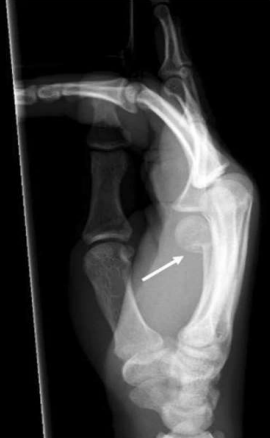

Figure 02 (a) AP radiograph showing a distal tuft fracture (arrow) (b) Typical clamshell splint used to protect a tuft fracture